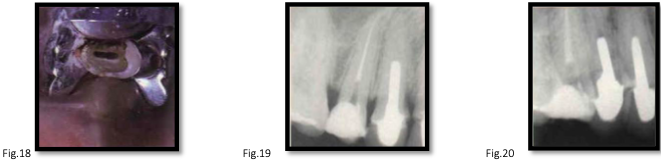

canal anatomy of mn 1st molar

roots: usually 2 (mesial and distal)

mesial root:

2 canals in 87% [fig. 42]

about half merge at apical foramen

canals curve mesially then gradually distal

mesiobuccal canal more curved than mesiolingual

canals may communicate along their length [fig. 43]

grooves on midline wall increase perforation risk [fig. 44]

distal root:

canal centrally located, slightly behind middle bucco-lingual fissure [fig. 45-47]

single canal cases: Broad bucco-lingually [fig. 48]

canal openings:

mesiobuccal → beneath mesiobuccal cusp

mesiolingual → nearer midline